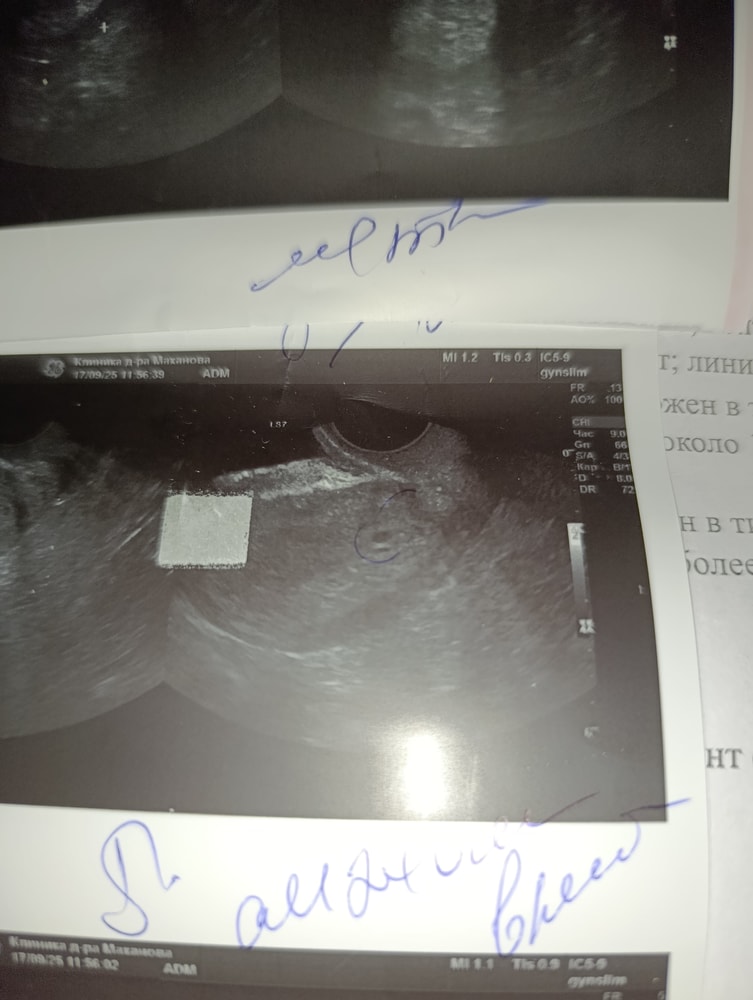

А на узи сказали что у меня кисты в эндометрии, кто сталкивался, подскажите пожалуйста

Сомнительный результат теста может быть связан с несколькими факторами - уровень хорионического гонадотропина может быть ещё слишком низким, либо есть ложноположительная реакция. Кисты в эндометрии иногда влияют на гормональный фон и могут давать подобные ситуации. Лучше сдать кровь на ХГЧ и пройти повторное УЗИ через несколько дней, чтобы отследить динамику.

Сдать хгч в динамике,думаю это беременность,просто на узи еще не видно,т к рано